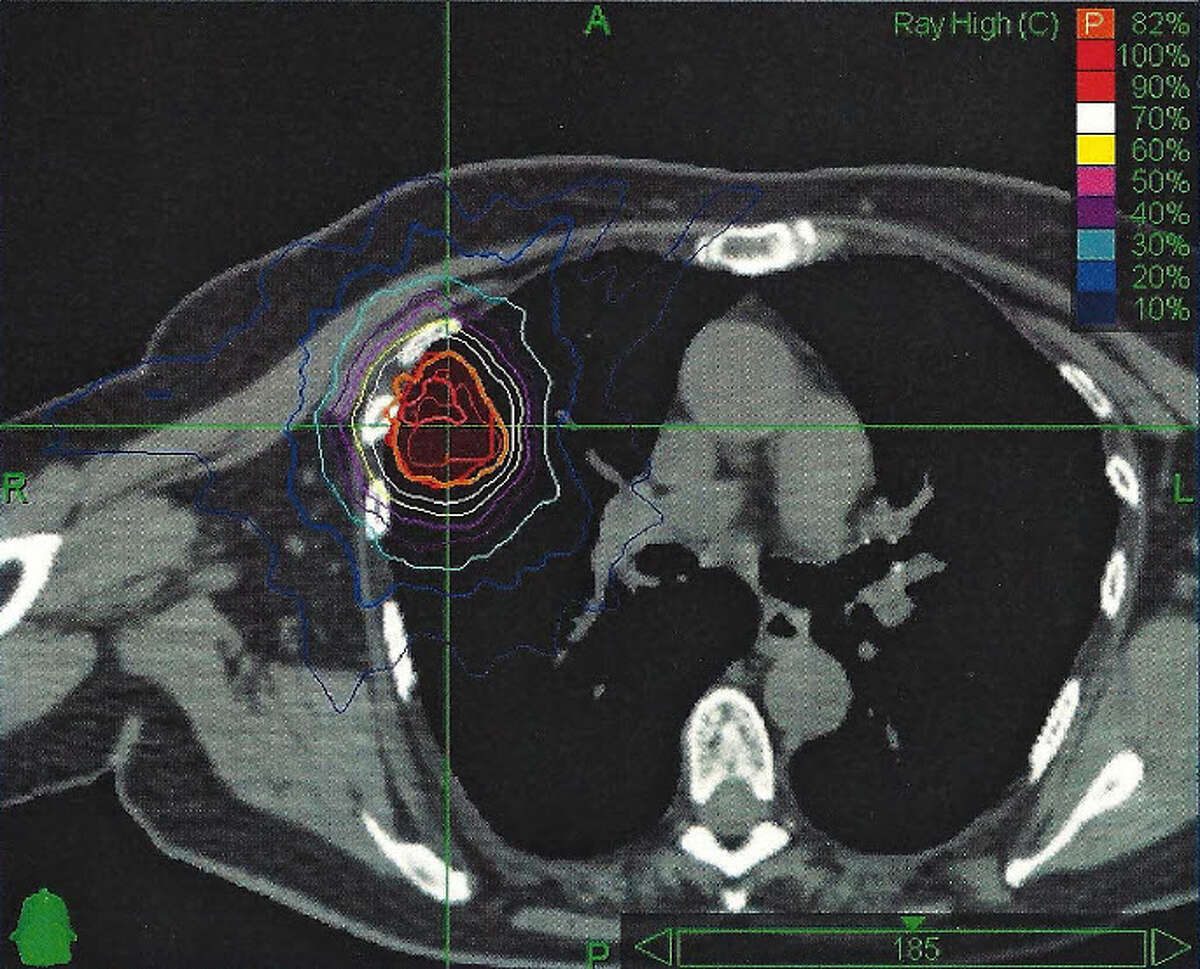

Focused radiation treatment targets lung cancer

Focused radiation treatment targets lung cancer Computer Effects Radiation laptop radiation is a serious concern for many. computer radiation protection is extremely important. In this article, i’ll share everything you. it’s important to know the emf radiation dangers associated with laptops and make smart decisions around usage and when you do have to use. In this organized guide, we'll go in depth about what laptop emf. Computer Effects Radiation.